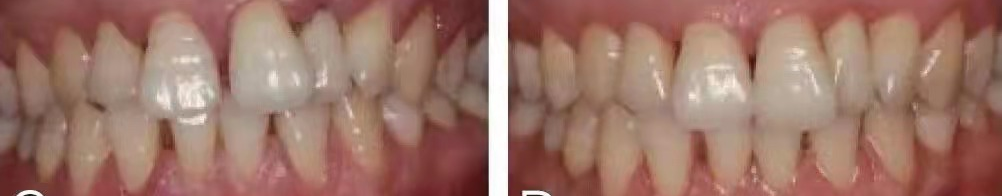

▲慢性牙周病引起牙松动的喷砂治疗前后对比图